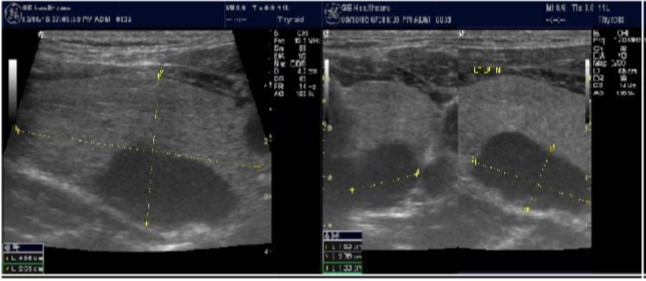

The reported prevalence of nodular thyroid disease depends on the population studied and the methods used to detect nodules 16. Our study population is unique as it is composed entirely of ESKD patients. We also used ultrasound as a method of detecting thyroid abnormalities. In our study the prevalence of thyroid nodular pathology as detected by ultrasound was found to be 57.6% mirror image what reported in the literature as it has been reported that nodules found on ultrasonography suggest a prevalence of 19 to 67%17, 18; and in other publications it has been reported to range from 50% to 70% 7, 8. Figure 3A below shows an Ultrasound detected thyroid nodule.

High-resolution ultrasonography (USG) is the most accurate and cost-effective method for evaluating and observing thyroid nodules 3. Although there is some overlap between ultrasound appearance of benign and malignant nodules, certain USG features are helpful in differentiating the two. Iso-or hyper-echogenicity of the thyroid nodule in conjunction with a spongiform appearance is the most reliable criterion for benignity of the nodule on gray-scale ultrasound, Figure 4A. Other features like nodule size <1 cm, width > length, presence of hypoechoic or hyperoechoic halo around the nodule, Figure 4A and Figure 4B, caused by fibrous capsule compressing thyroid tissue, and coarse/curvilinear calcification are less specific but may be useful ancillary signs4 ,6. "Ring down" or "comet-tail" artifact or sign is typical of benign cystic colloid nodule, Figure 520. Perinodular flow or spoke-and-wheel-like appearance of vessels on color Doppler examination is characteristic of a benign thyroid nodule. However, this flow pattern may also be seen in thyroid malignancy. A complete avascular nodule is very unlikely to be malignant 4.

In our study many patients were found to have nodules look very much like PT adenoma, Figure 7 below. At least, 4 patients were subsequently confirmed to have parathyroid adenomas, Figure 8 and 2 patients underwent surgery

Despite the fact that nodular pathology was found to be very prevalent among our study population, it has been found difficult to differentiate between thyroid and parathyroid pathology using ultrasound alone. However, some characteristics of the parathyroid glands might suggest parathyroid pathology in the context of the clinical picture of secondary or tertiary hyperparathyroidism which is very prevalent in ESKD patients’ populations.

Figure 7.Thyroid nodule suspicious for Parathyroid adenoma due to its location

Figure 8.Nodule that proven to be a parathyroid adenoma, volume =5265 mm3